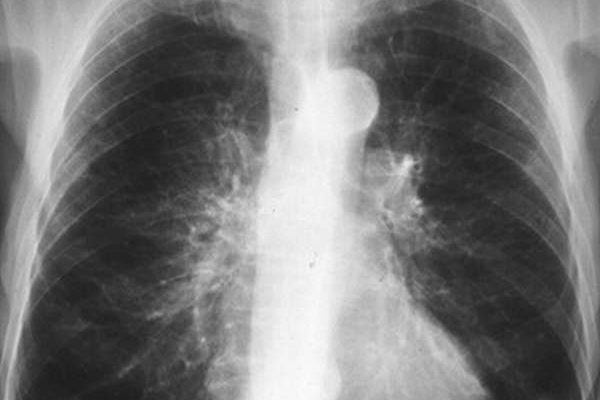

Простой острый бронхит на рентгеновских снимках не виден, визуализируется только обструктивная и хроническая длительная форма заболевания. Давайте рассмотрим примеры того, как выглядит бронхит на рентгеновских снимках:

На фото 1 и 2 показано, как выглядит бронхит на рентгеновских снимках, точнее, каковы симптомы заболевания:

- изменение размеров и структуры корней легких;

- размытость контуров;

- изменение картины легких (обычно усиление);

- Утолщение бронхиальной стенки при хроническом бронхите (симптом «трамвайных рельсов» — фото 3).